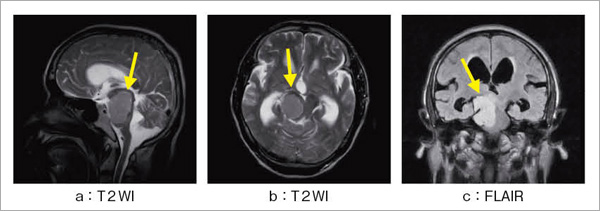

MRI検査 | きたがわ脳神経外科 | 北九州市八幡西区本城学研台の。APERTO Inspireと“癒し”を与える独自のシステムで快適なMRI検査。検査機材について|動物検診センター キャミック | 動物検診。検査機材について|動物検診センター キャミック | 動物検診。緑と黒のドレスを着た女性のポートレート